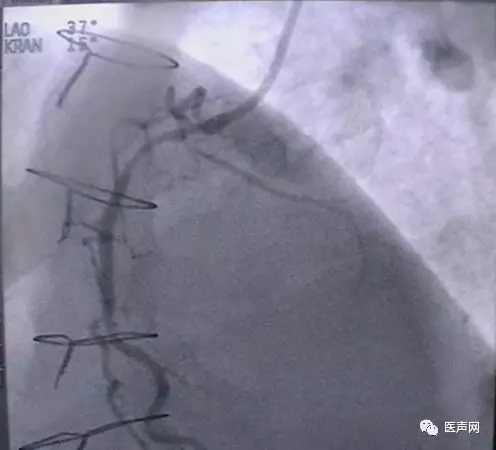

病例2:RCA 支架术后,近端CTO

CAG:RCA 支架术后,近端至远端支架,近端慢性闭塞病变(CTO)(下图所示)

手术经过:AL1.5导引导管,然后换AL2.0导引导管,在微导管支撑下,用硬导丝通过病变,直径1.25mm球囊至远端,远端有夹层,重至真腔,

但近端不确定是否真 腔,2.0mm CTO球囊可至RCA中段,导引导管弹出,重新进入,但近端可能是假 腔,终止手术,下次再试。

近端导丝在支架轮廓外侧

有3个Mark标记者为微导管,微导管可达RCA远段,但不一定在支架内走行。